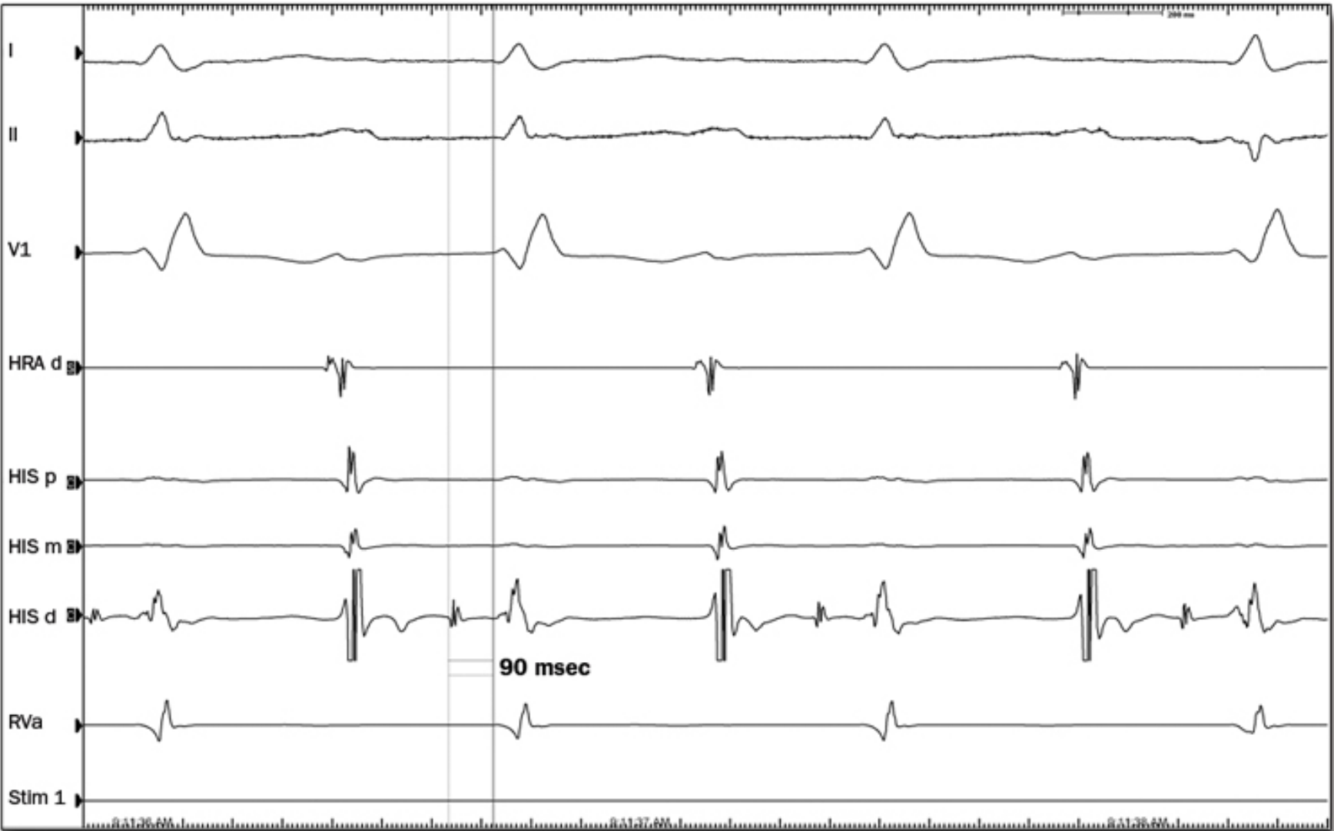

Leads I, II, and V1 = surface tracings recorded at a speed of 100 mm/sec (faster than speed of surface ECG which is 25 mm/sec)

HRA d –> High RA placement

HIS bundle catheter (HIS p, m, d)

-AH time can be measured from the low RA recording (HIS p) and the bundle electrogram (HIS m, d)